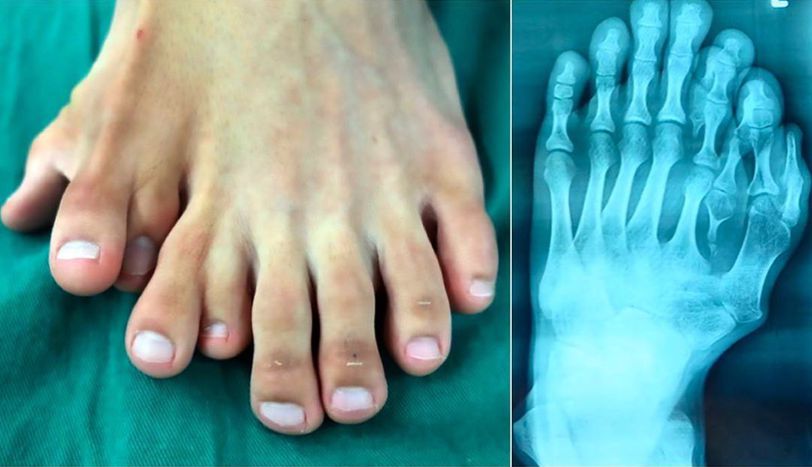

This is a condition called polydactyly — supernumerary (or accessory) fingers and/or toes! The 21-year-old man born with nine toes on his left foot had the four extra digits surgically removed after a lifetime of living with the deformity. The patient said the 4 extra toes on his left foot had caused him so much stigma he stopped wearing sandals when he was 10 and been too embarrassed to go on a date. The X-ray shows smaller digits sprouting out of normal-sized toes, and a lack of a big toe. His parents were aware of his condition as soon as he was born, but they refused to let doctors operate on him. They sought the advice of a fortune teller instead, believing that his extra toes were ‘a gift from the heavens’ which shouldn’t be removed. Seeking a reversal of fortune, he sought out expert advice. It’s very rare to see such a serious deformity having not been treated in a 21-year-old patient. Removing his outermost extra toes would’ve been the easiest solution, but it wouldn’t look the best. His most natural looking toe is on the outside, so doctors decided to migrate it inwards to its most ideal position, replacing his fifth digit and creating a new big toe. The surgical team spent 9 hours in surgery to create the patient's new left foot. Polydactyly is classified as either preaxial (duplication medial to the first toe), central (duplication around the second to the fourth toes), or postaxial (duplication lateral to the fifth toe), the latter of which is the most common. The toe may be rudimentary (without osseous structures) or a complete digit with its own metatarsal. This patient had complete central and postaxial duplications. Because protruding toes can cause problems with the fit of footwear in the future, the decision to remove them usually is made before the child begins to walk. The ideal age at which to remove supernumerary toes is between 9 and 12 months. At this age, the foot is large enough to make excision simple, and the child is less aware of the problem. Simple resection of the extra toes is generally sufficient, especially in cases of postaxial deformity.

All 9 toes are remarkably well formed including toe nails!